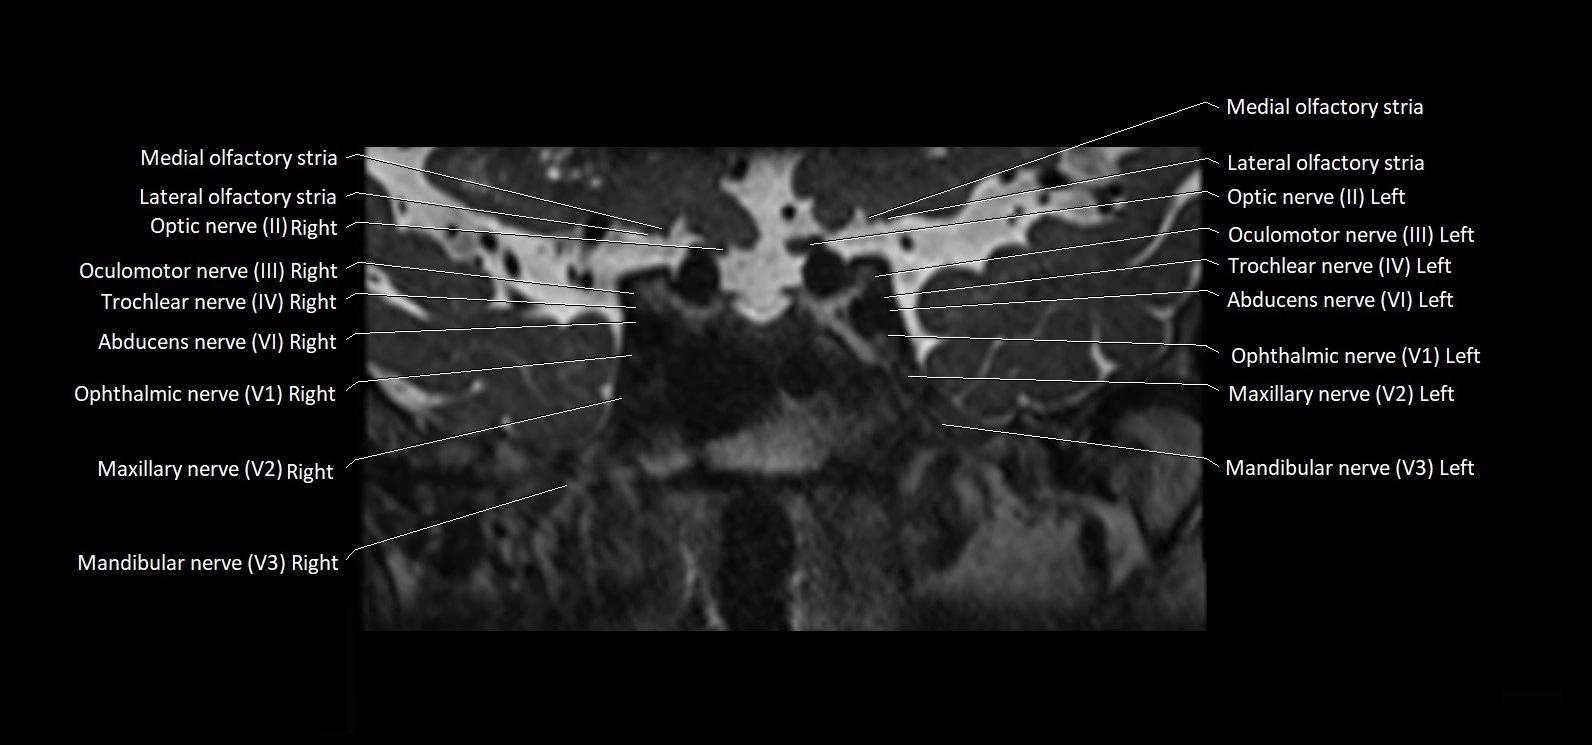

MRI images

image